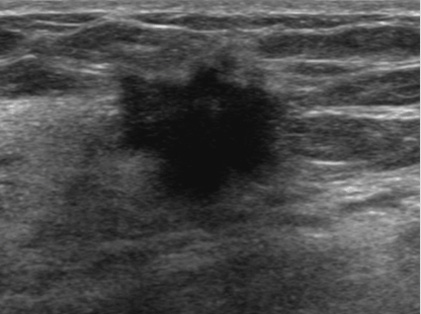

◆ 결절의 특징

1) 모양 : 불규칙하거나 찌그러진 모양의 결절은 암일 가능성이 높습니다.

2) 경계 : 경계가 명확하지 않고 주변 조직과 침범하는 형태의 결절은 암일 가능성이 높습니다.

3) 크기: 일반적으로 2cm 이상의 결절은 암일 가능성이 높습니다.

4) 성장속도: 빠르게 성장하는 결절은 암일 가능성이 높습니다.

ㆍ유방 초음파 : 초음파를 이용하여 유방의 내부를 관찰하는 검사입니다. 유방을 압박하지 않고 검사할 수 있으며 통증이 없습니다. 또한, 유방의 모든 조직을 관찰할 수 있어 유방암의 조기 발견에 효과적입니다.